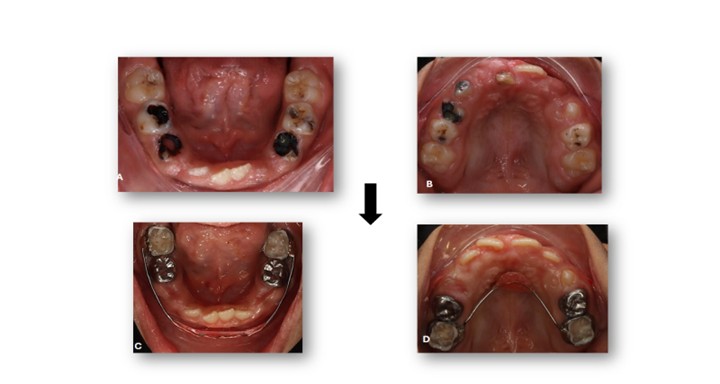

At the one-week postoperative review, healing was satisfactory, with no signs of infection or discomfort. Two weeks later, a multidisciplinary consultation among pediatric dentistry, orthodontics, and periodontics was conducted. Interceptive orthodontic treatment was initiated using a Nance appliance in the upper arch to preserve space and prevent mesial drift of posterior teeth, and a lip bumper in the lower arch to reduce lip pressure and support arch development (Figure 6). A lingual holding arch was planned for subsequent placement following the full eruption of the lower permanent teeth.

Figure 6: Pre- and Post-Operative Records. Intraoral occlusal photographs. A, B) Pre-operative views showing extensive caries and tooth structure breakdown. C, D) Post-operative views showing restored teeth and improved oral condition with placement of a Nance appliance in the upper arch and a lip bumper in the lower arch.